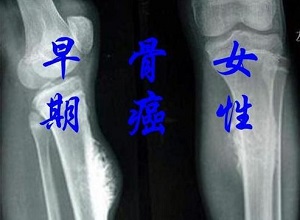

癌症在现代医学领域仍然是一个相对困难的研究课题,许多患者在生病后开始了解疾病的原因。骨癌是一种近年来比较高发的一种癌症,其严重程度不容忽视。让我们了解一下,是什么因素导致了骨癌的发生:

骨癌的病因-物理因素是各种电离辐射,如X射线照射、镭、氢、锶、放射性同位素等。这些电离辐射可以通过体外或体内辐射诱发骨癌。其中,骨癌的常见病因也度放疗而导致骨肉瘤。临床上,这种骨瘤被称为放射后骨肉瘤。

某些骨瘤疾病的恶性转化也是骨癌的一个形成因素,因此软骨瘤的出现。成骨细胞瘤、骨软骨瘤等良性骨肿瘤,或肿瘤样病变,应及时治疗,防止良性肿瘤恶性转化形成肉瘤,从而损害健康,这是骨癌的常见原因。骨癌的发生可能与生物学特征有关。或疾病期。手术。感染和病理性骨折。